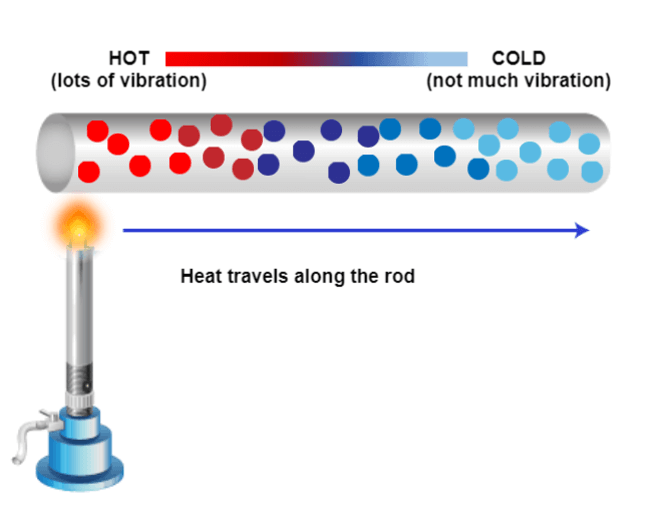

Metals can be conductors of heat and electricity. Previously, we learned about how introducing a magnet into a closed coil can increase voltage. This can be a concern with certain metals in the magnet. The conductors can be dangerous under certain conditions, which we will discuss in a bit.

One of the great principles of physics is that energy cannot be created or destroyed. Thinking back to Faradays Law, we learned that during the process we are creating a current with the varying magnetization. A portion of the energy created will be in the precession and subsequent relaxation and signal that is produced. But not all of the energy becomes signal. Some are heated. Where does this heat get deposited? Usually within the patient.

However, if there is something present that works as a conductor, the heat may be deposited there. We mentioned metals as conductors but other materials may conduct also. If any of these conductors are touching the patient’s skin or internal organs, and RF (radiofrequency) burn may occur.